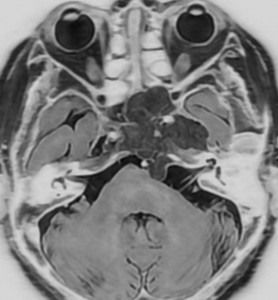

T2強調画像で高信号となるのは脊索腫と同様です。斜台後方の硬膜を破って前橋槽に伸展しています。これも脊索腫と同じような伸展浸潤形態と言えます。

骨軟骨腫が若い時からあって壮年になってから悪性化した軟骨肉腫です。20代のときに右外転神経麻痺が生じて20年以上そのまま経過しました。左のCTでは頭蓋骨の真ん中の斜台というところに異常な骨があって,良性の骨軟骨腫のように見えます。でも右側のMRIでは脳幹部に深く食い込む柔らかい腫瘍の部分が写っていてこれは軟骨肉腫を疑う像です。手術摘出と術後の放射線治療をしました。